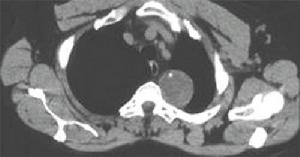

4、CT及磁共振:可明確顯示心包增厚的程度,陽性率占80%左右。高速CT(UFCT)更為準確。磁共振是診斷縮窄性心包炎的最佳無創性檢查,可準確測量心包厚度以及右心房擴張與右心室縮小的程度。